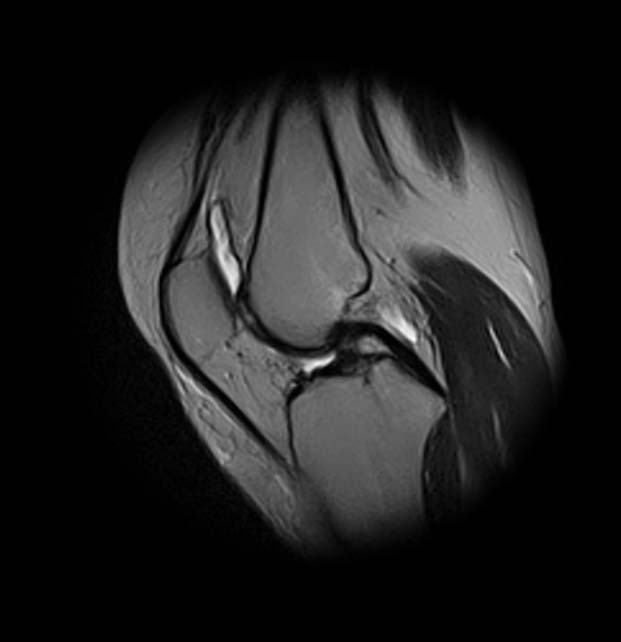

[Ortho] Показания для артроскопии

1. травма 5 лет назад - "ударилась коленом", с тех пор боли в суставе

3. стандартные рентгенограммы с небольшими изменениями - сужение

медиальной суставной щели

4. вес пациентки 80 кг, рост 165

5. сустав клинически стабилен